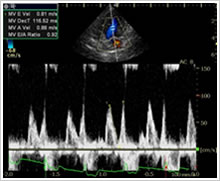

超音波検査(別名エコー検査)は身体への負担が少ない低侵襲の検査ながら、多くの情報が得られる、診断に有用な検査として知られています。当院では専任のベテランの技師による、頸動脈、甲状腺、心臓、腹部の検査を実施しております。

心臓PWD波形